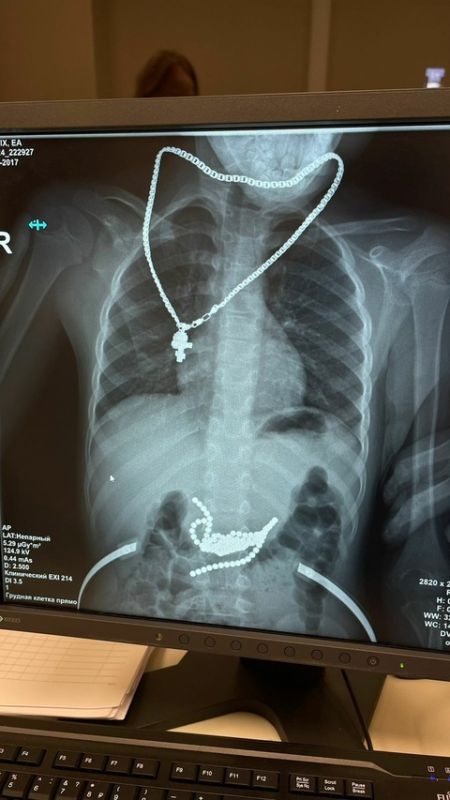

Узнав о произошедшем, родители поспешили в больницу. Рентген показал, что магнитные шарики уже начали притягиваться друг к другу, вызывая предперфорацию стенки желудка и 12-перстной кишки. Если бы ребёнок рассказал о случившемся на пару часов позже, последствия были бы гораздо серьёзнее.

Чтобы достать детали игрушки, врачи вскрыли желудок и кишечник малыша. Неодимовые шарики, обладающие самой большой силой магнетизма, успешно извлекли.